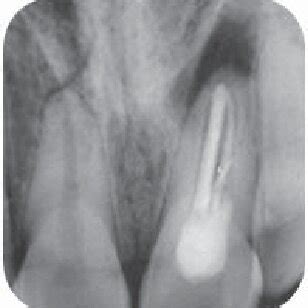

La radiografía inicial reveló un conducto lateral que había sido rellenado con cemento obturado al colocar la gutapercha en el conducto principal. Durante la reendodoncia, fue crucial retirar este cemento.

Con cloroformo y paciencia, se eliminó la mayor cantidad posible del material. Se instrumentó hasta el ancho y largo necesario (determinado al tacto y con el localizador de ápices) y se desinfectó el diente siguiendo el protocolo establecido. En esta ocasión, se utilizó dique de goma para asegurar el aislamiento adecuado.

Ahora queda esperar unos meses a la recuperación de la lesión. Se necesita mínimo 4 meses para ver una diferencia de la regeneración del hueso en las radiografías periapicales. Al menos, la paciente se va sin molestias y con el diente limpio y debidamente rellenado, y eso nos deja tranquilos. No nos cabe duda de que la lesión se curará.